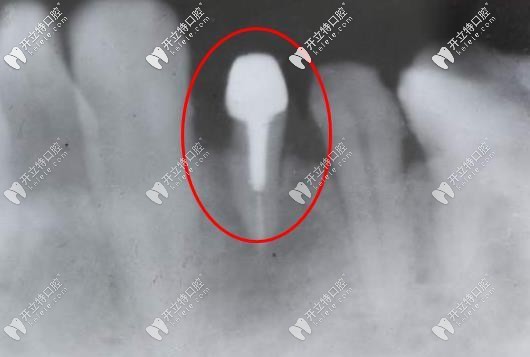

打樁后的牙片

注意事項(xiàng):做過(guò)根管治療的牙齒一般會(huì)比較脆,所以牙醫(yī)一般會(huì)建議做纖維樁,可以減少根裂的幾率,在做治療的時(shí)候,一定要拔牙齒的所有情況告訴醫(yī)生,這樣更便于醫(yī)生診療。